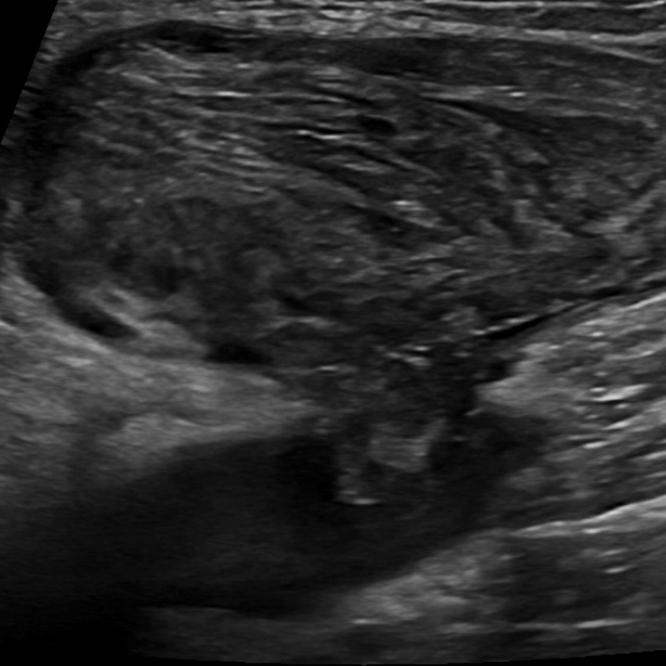

Endovascular filter-protected resection of a large primary great saphenous vein aneurysm containing thrombus.

J Vasc Surg Venous Lymphat Disord. 2024 Sep;12(5):101845. doi: 10.1016/j.jvsv.2024.101845. Epub 2024 Feb 3.